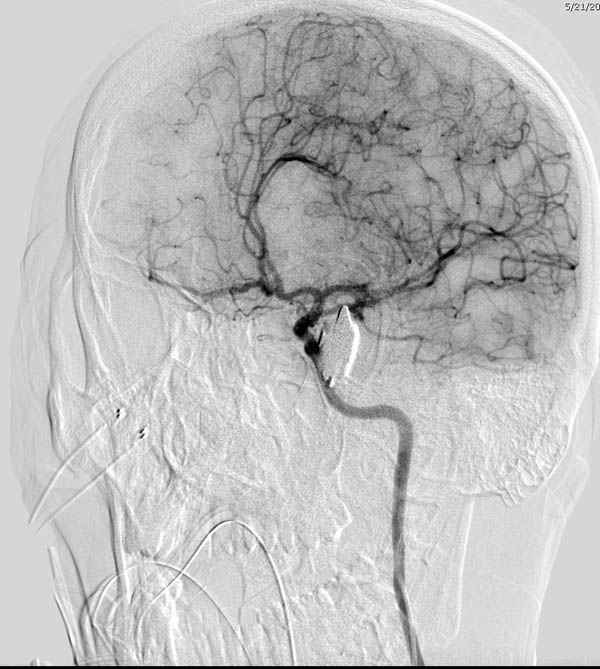

По протоколу сделаны все необходимые исследования: рентген, ангиограмма с 3Д реконструкцией, где обнаружили что все жизненно важные сосуды не задеты, даже некоторые "сидят" изгибаясь на ноже.

Одним махом нож удалить не удалось, пришлось раскачать и потом двумя руками удалили нож. Рана без кровотечения, обработана и зашита.